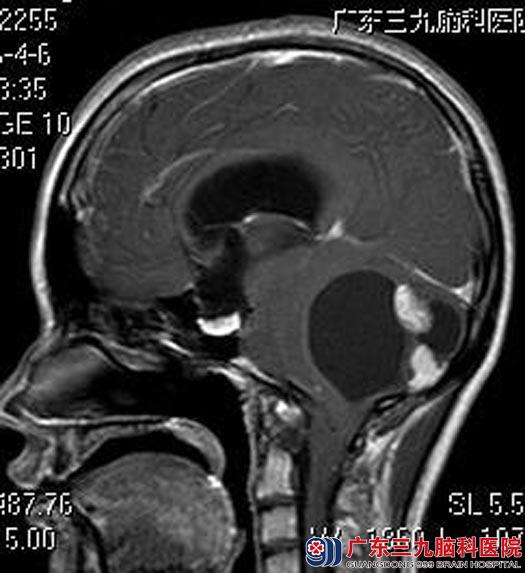

婷婷的父母立即带着她来到广东三九脑科医院,头颅MR检查提示:右侧小脑半球占位性病变,病灶大小约为6.6cm×5.8cm×5.1cm,增强后壁结节呈明显不均匀异常强化影,囊壁未见明显强化。四脑室受压变窄,脑干受压变形,小脑扁桃体变尖,向下疝入枕骨大孔,幕上脑室系统明显扩张,考虑毛细胞星形细胞瘤可能,待排血管母细胞瘤。